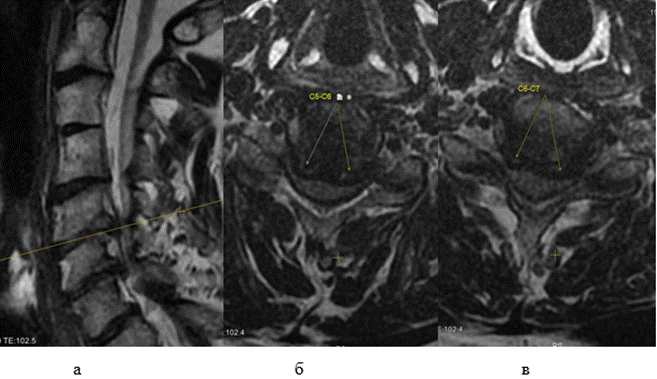

На момент осмотра выявлены: болевой синдром по ВАШ - 6 баллов; ASIA -двигательная функция (ДФ) 27 баллов, тактильная чувствительность (ТЧ) 60 баллов, болевая чувствительность (БЧ) 30 баллов; имелась задержка функции тазовых органов; по Frankel группа здоровья A; NDI - 28 баллов; SF-36: физический компонент здоровья (ФКЗ) - 11,25% и психологический компонент здоровья (ПКЗ) - 9,5%; EAT-10 - дисфагия 6 баллов; ИМТ - 18,3 балла. По данным МРТ шейного отдела позвоночника у пациента имелось сужение просвета позвоночного канала, преимущественно за счет диск-остеофитных комплексов, на уровне С4-С5, С5-С6, С6-С7 межпозвонковых дисков (рис. 1а), максимальная передняя компрессия спинного мозга определялась на уровне С5-С6 (рис. 1б) и С6-С7 (рис. 1в).

Рис. 1. Фото предоперационных МР-сканов шеи пациента мужского пола 71 года: а- сагиттальная проекция; б – аксиальная проекция на уровне диска С5-С6; в - аксиальная проекция на уровне диска С6-С7 (составлен авторами по результатам данного исследования)